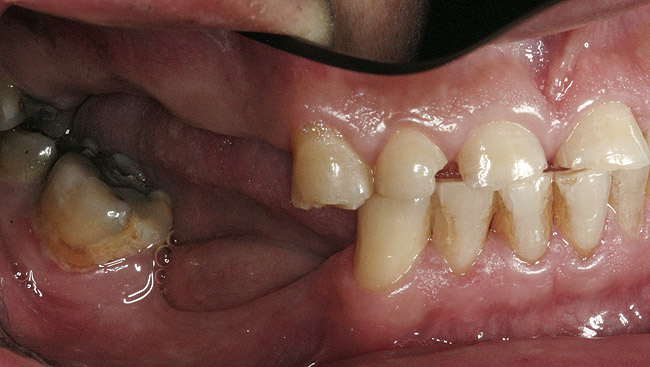

Figure 6  Lateral right view.

Figure 6

Figure 7  Lateral left view.

Figure 7

Initial examination revealed a partial edentulous patient with extensive wear of the maxillary anterior teeth and moderate wear in the mandibular teeth (Figure 1, Figure 2, Figure 3 , Figure 4, Figure 5, Figure 6 and Figure 7). The patient's maxillary and mandibular RPDs also showed excessive wear and multiple signs of fractures (Figure 2 and Figure 3). The patient had been wearing a mandibular nightguard for 8 years.